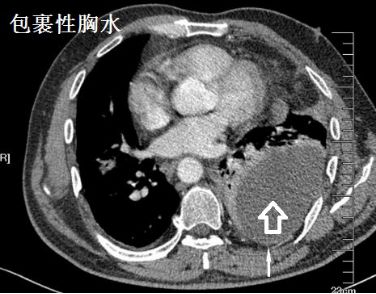

蜘蛛网胸水,也叫蜂窝状胸水,我发明的词汇,专业场合请用“包裹性胸水”!要不然查病历的把你这个月那点可怜的毛工资扣得连毛都没有!

蜘蛛网胸水(包裹性胸腔积液),在胸腔镜下是什么鬼样子的呢?

一大包胸水,看着是不是很好抽?Ease,轻松搞定!

为什么会酱紫?明明有胸水啊!明明确实有胸水,只不过......

且看胸腔镜:

胸腔里面这么多分隔,你能保证你的针在哪个小分隔里面?除非你有孙悟空的火眼金睛!

对于包裹性积液,胸腔积液粘稠或分隔形成,B超下的表现,如下图: